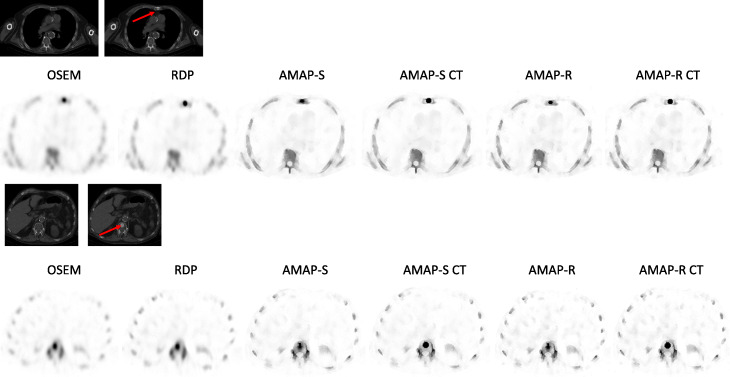

Fig. 2.

Example reconstructed SPECT and CT (with and without lesions) transverse slices at the level of sternum and spine lesions of the male patient study with artificial lesions. Red arrows show the lesion locations. VOI used to analyze the reconstructed SPECT studies had the same shape and position as the lesion seen on the CT image. AMAP-S and AMAP-R refer to reconstructions where lesion is absent in the CT and AMAP-S CT and AMAP-R CT to lesion-present cases. The color scale is set to SUV 15 for all SPECT images

Table 2 presents SUVmax and SUVmean for the artificial lesions for the four reconstruction methods. The three Bayesian methods provide SUVmean values, which are closer to the true SUV value (SUV = 15) than OSEM for all lesions. The improvement in SUVmean accuracy is dependent on the lesion location, and interestingly, RDP partly provides more accurate SUVmean estimates than AMAP-S in cases where the lesion is not present in the CT. AMAP-R offers the largest improvement independent of the lesion location. Reconstructions with lesion-present CTs perform considerably better than reconstructions with lesion-free CTs. Lesion-present CTs also render AMAP-S and AMAP-R lesions into the correct shape and size as can be seen from Figs. 2 and 3. SUVmax values overshoot the true SUV value with all Bayesian reconstruction methods. AMAP-S and AMAP-R reconstructions with lesion-present CTs (AMAP-S CT and AMAP-R CT) partly reduce this overshoot, but cannot completely mitigate it. Average relative error (= 100 × (SUVmean − 15)/15) in SUVmean for OSEM, RDP, AMAP-S, AMAP-S CT, AMAP-R, and AMAP-R CT is − 53%, − 35%, − 40%, − 15%, − 30%, and − 10%.

AMAP-S and AMAP-R reconstructions with matching CT lesions produce the most accurate results (Table 2) especially in terms of SUVmean. They preserve the correct lesion size and shape (Figs. 2 and 3). The appearance of lesions is overall quite different with AMAP-S and AMAP-R when compared to OSEM or RDP (Figs. 6 and 7). Reconstructions with anatomical prior information force bone lesions in SPECT images to follow bones and not to extend outside the bone boundaries (Fig. 7).